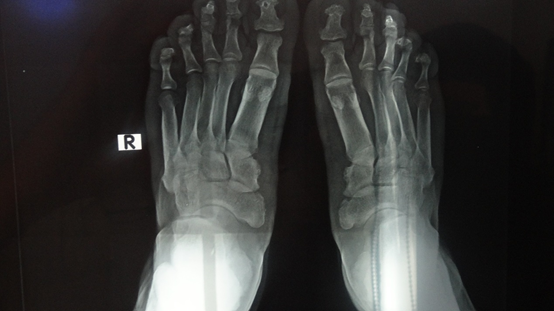

On cutaneous examination, the patient had thickened and moist fingers and toes, digital clubbing, and deep creases on the forehead and scalp (Figures 16). Initially, acromegaly was considered; however, the absence of facial features such as an enlarged nose, chin, and tongue made this diagnosis unlikely. Radiographic imaging of the hands and feet showed periostosis of the fingers and toes, confirming pachydermoperiostosis (PDP).

Figure 6 Foot X-ray revealing periostosis of the toes, tibia, and fibula.